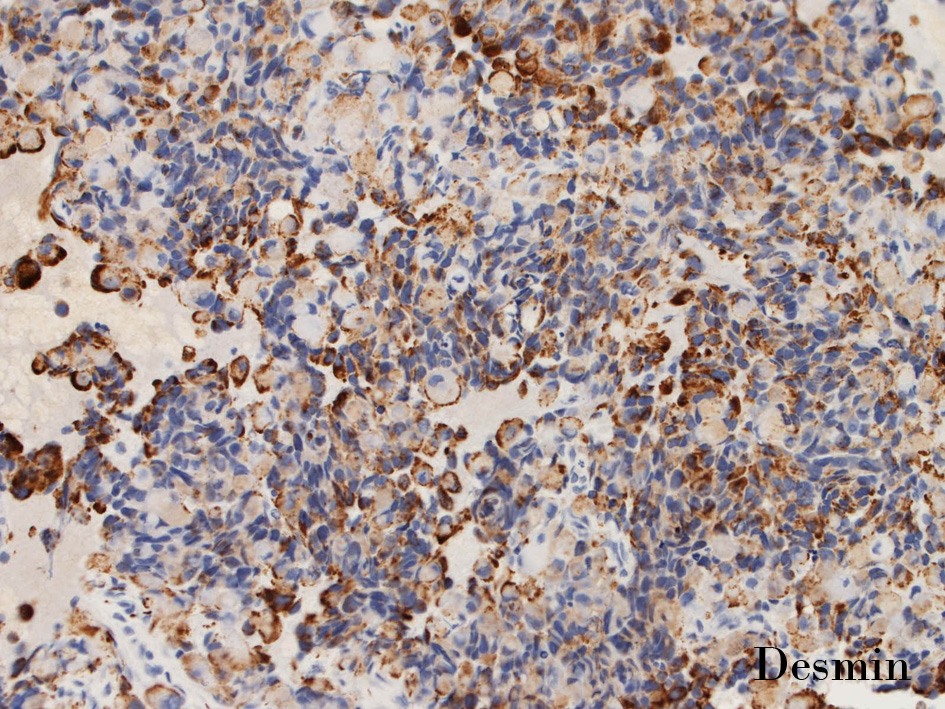

DesminDesminmyogenin

small round cell tumorの中でrhabdomyosarcomaは腫瘍細胞に種々の抗原が陽性となるため診断を誤ることがあり注意が必要である*1

*1 Bahrami A, et al., Aberrant expression of epithelial and neuroendocrine markers in alveolar rhabdomyosarcoma: a potentially serious diagnostic pitfall. Mod Pathol. 2008 Jul;21(7):795-806. Epub 2008 May 16. PMID:1848799199